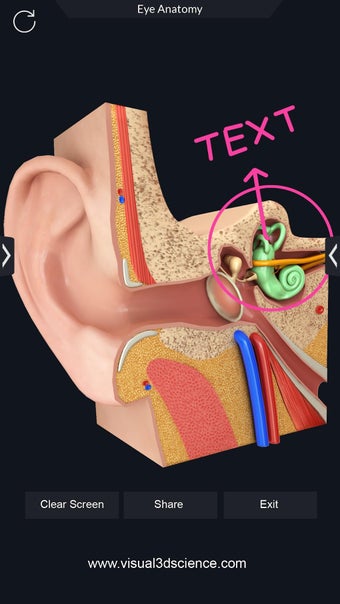

La interfaz fácil de usar de My Organs Anatomy permite una navegación sencilla, lo que facilita la selección, rayos X, ocultación y visualización de órganos individuales. La aplicación también incluye un modo de animación, opciones de búsqueda y un panel de información que proporciona información relacionada. Además, la aplicación ofrece pronunciación de audio para todos los términos anatómicos, e incluso los usuarios pueden dibujar o escribir en la pantalla y compartir capturas de pantalla.